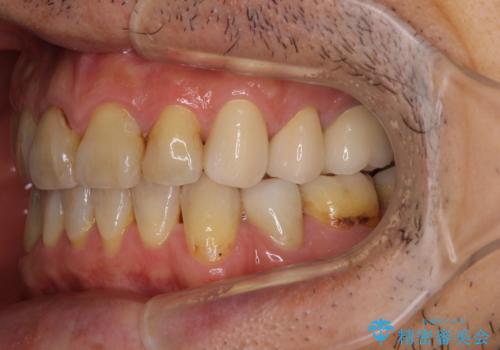

- むし歯による奥歯の痛みを気にして来院された患者様です。

神経にまでむし歯の及んでいる歯や、既に根管治療がされている歯に痛みがあったため、まずは根管治療を行うこととしました。

その後、以前行った抜歯矯正の後戻りをインビザライン・ライトにより改善し、むし歯や銀歯はオールセラミッククラウンにて補綴治療することとしました。

痛みは速やかに引き、銀歯や黒く変色したむし歯がセラミッククラウンで自然な色合いに仕上がり、患者様には大変満足していただきました。